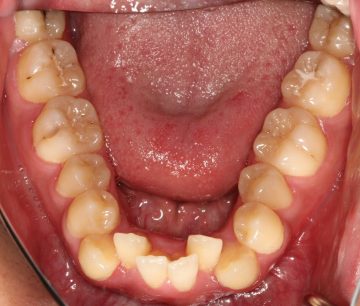

下顎前突(反対咬合、上あごの劣成長等を含む)の矯正症例

(24歳 男性 )

小臼歯4本抜歯によるマウスピース型カスタムメイド矯正装置(インビザライン)単独による治療

治療前

治療後